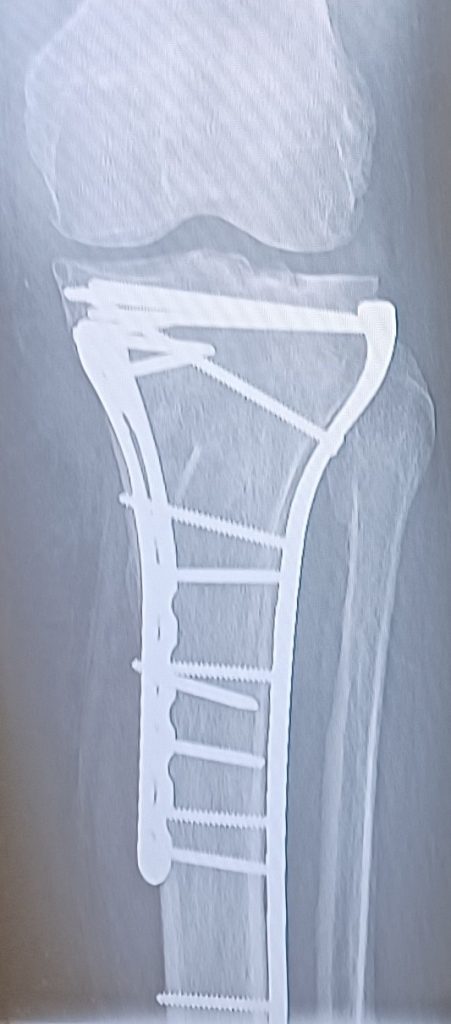

After 3 years recovered from my hip replacement surgery; Boom! Crack! Trauma! I fell and broke my knee and ankle. More specifically, a plateau fracture and a broken ankle. My tibia and fibula. Oh my goodness.

The ambulance came and transported me within an hour. I was checked in to my room and saw Dr. Aleksey Dvorzhinskiy that evening after I arrived. He had just finished another surgery and he was confident, kind, caring, smart and responsive to my needs. He reviewed my x-rays and scheduled my surgery.

Later that night, Dr. Dvorzhinskiy came to my room to visit with me and went over my new x-rays the next day. He showed me all the hardware that was inside my ankle and knee.

I met with Dr. Dvorzhinskiy every month to follow up on my progress with healing and physical therapy. I was also amazed at the minimal pain and healing of my incisions. Dr. Dvorzhinskiy is a master surgeon and yes he played with erector sets and Legos as a child thank God lol!